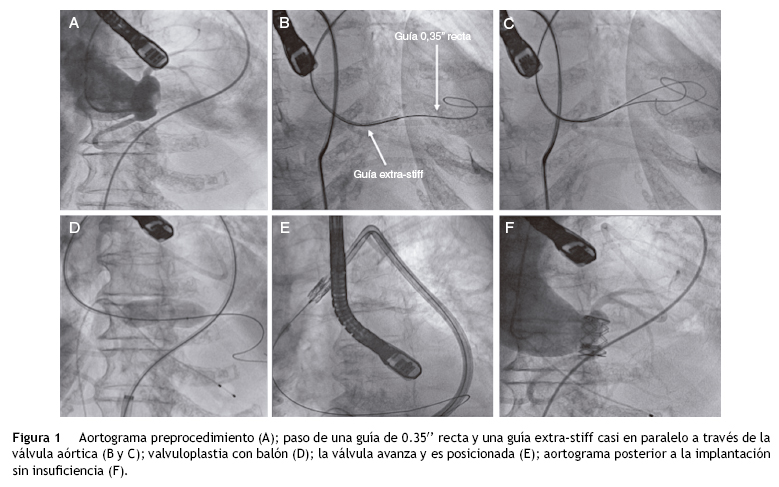

Con los avances en la tecnología, en nuestros tiempos se pueden tratar válvulas aórticas en pacientes con aortas muy tortuosas que antes eran consideradas una contraindicación para el implante de válvula aórtica percutánea. Se describe el caso de una mujer de 86 años con estenosis aórtica sintomática, diabetes, hipertensión arterial, dislipidemia y fibrilación auricular crónica. Se realizó un ecocardiograma transesofágico que demostró una estenosis aórtica, con un área valvular de 0.56 cm2 (0.40 cm2/m2) y un gradiente medio de 82 mmHg. El diámetro del anillo fue de 19 mm, con insuficiencia aórtica leve; y una fracción de expulsión del ventrículo izquierdo del 55%. En la coronariografía se observaron arterias coronarias sin lesiones significativas y en el aortograma una aorta extremadamente tortuosa y una aorta ascendente en posición horizontal con respecto al plano valvular5,6 (fig. 1A). En la sesión médico-quirúrgica se concluyó que la paciente tenía un EuroSCORE logístico del 12% y alto riesgo quirúrgico por presentar una deformidad torácica importante. Por estas razones se decidió realizar implante percutáneo de válvula aórtica6. Se utilizó como acceso terapéutico (acceso arterial donde se sube la prótesis) la arteria femoral común izquierda con un introductor expandible 18 Fr (E-Sheath). La marcada tortuosidad de la aorta torácica hizo el acceso difícil solo para cruzar la válvula aórtica y especialmente el intercambio de la guía recta 0.35" por la guía Amplatz extra-stiff (Cook Medical Inc, Bloomington, Ind., EE. UU.). Se decidió utilizar un catéter terapéutico multipropósito de 7 Fr, y con las 2 guías en paralelo en la punta del catéter se introdujo la guía recta dentro del ventrículo izquierdo para pasar inmediatamente la guía extra-stiff (fig. 1B y C) preformada dentro del ventrículo izquierdo y no se observó ninguna dificultad en el resto del procedimiento. La valvuloplastia se realizó de manera habitual con el balón de 20 mm (fig. 1D), y se avanzó la válvula Edwards SAPIEN XT (Edwards Lifesciences, EE. UU.) n.° 23 sin dificultad y con apoyo del catéter liberador NovaFlex (fig. 1E). Se posicionó la válvula y fue implantada con la estimulación ventricular rápida. En el aortograma posprocedimiento no se observó insuficiencia aórtica, y el ecocardiograma periprocedimiento mostró una excelente aposición de la prótesis sin insuficiencia (fig. 1F). La paciente fue dada de alta a los 7 días sin complicaciones. En el ecocardiograma antes del alta se confirmó una adecuada posición de la válvula con un gradiente medio de 10 mmHg, sin insuficiencia aórtica. En el seguimiento clínico al año, la paciente se encontró en clase funcional I de la NYHA.